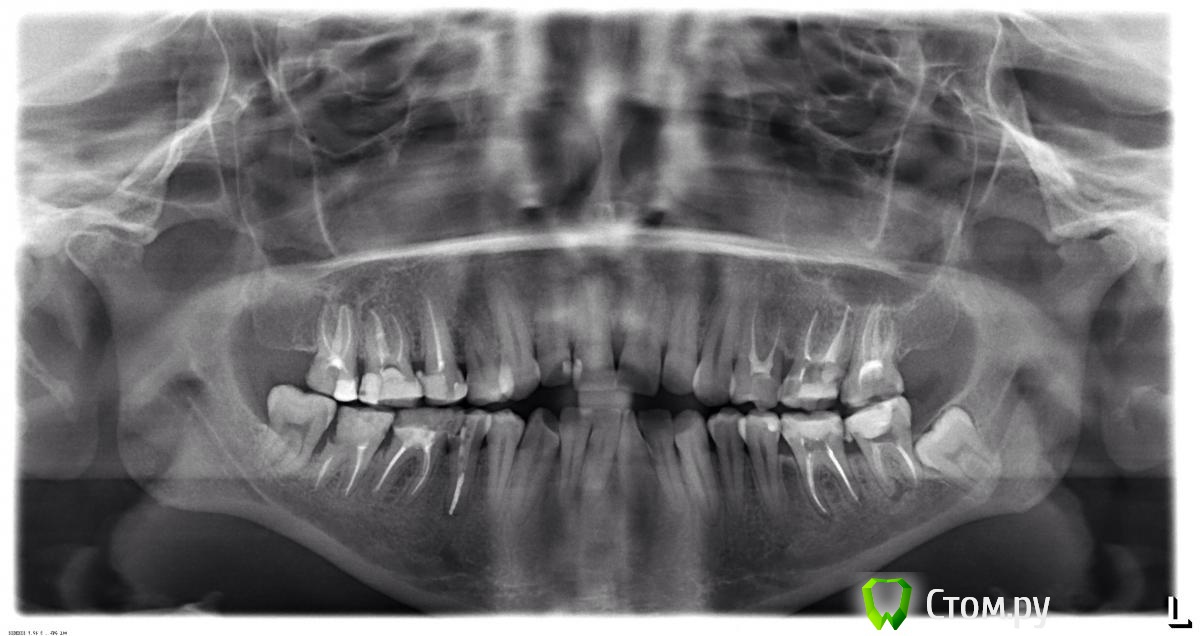

Stolga Опубликовано 17 ноября, 2014 Поделиться Опубликовано 17 ноября, 2014 Добрый день! 35 лет. Была на консультации у трех ортодонтов, хотела исправить прикус. Отказались брать. Причина: 1 - очень плохая эмаль, говорят за два года все зубы будут в кариесе; 2 - нижний зуб мудрости слева "лежит" глубоко и не может прорезаться, давит на весь ряд, удалять его боятся. Подскажите, пожалуйста, что можно сделать в моей ситуации. Спасибо. Ссылка на комментарий